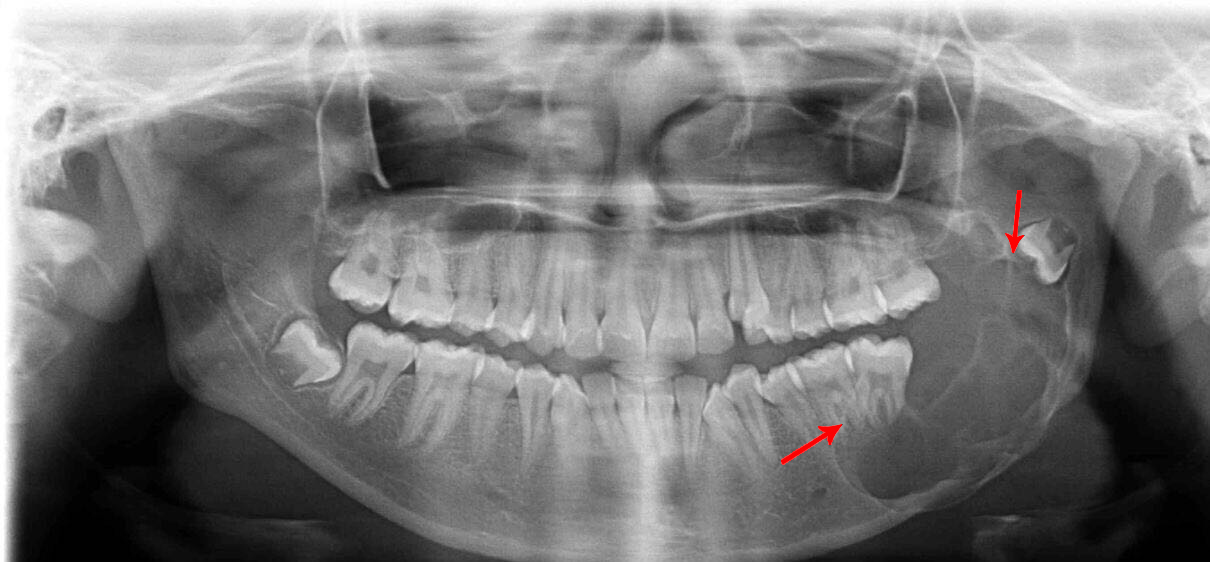

There are numerous pathologies that can develop in the jaws ranging from small cysts which are incidentally found on routine radiographic examination to large cysts which can cause facial swellings or asymmetry. To understand the type of pathology we usually do a biopsy. The biopsy may be an Incisional biopsy or an excisional biopsy. This is based on the surgeon’s opinion and the nature and the size of the lesion or growth in the jaws.

Using laser we can do the biopsy as a bloodless procedure. The vast array of pathologies, and the wide range of treatment they require ranging from simple laser excision to jaw resection is why you have to consult an oral and maxillofacial surgeon as early as you see something abnormal in your face or inside your mouth. The abnormality can even be as simple as a non healing ulcer or a small tissue tag inside the mouth.